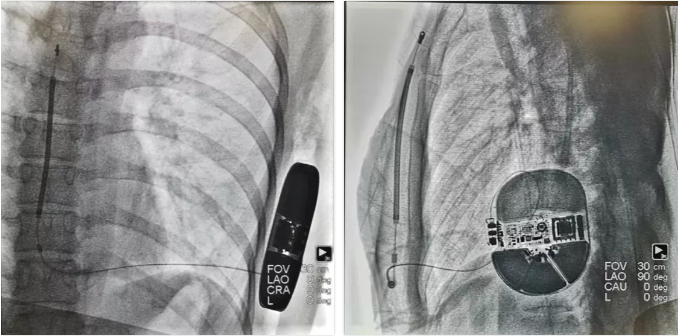

手术经过

手术在全身性麻醉下进行,分别于患者左侧第5肋间沿腋中线和剑突下右1cm切开皮肤,逐层分离皮下组织至深筋膜,通过皮下隧道导引针连接囊袋后,再沿胸骨向上电极标记处切开皮肤,逐层分离皮下组织至筋膜层,通过皮下隧道导引针将电极分别从囊袋经隧道送至剑突下切口,固定电极中段后,再使用皮下隧道导引针将电极经隧道送至胸骨上方切口,固定电极头端。

S-ICD成功植入

对所有伤口区进行有效止血,按压将隧道内空气排出。随后连接除颤装置,置入囊袋并逐层缝合皮下组织和皮肤,术区纱布覆盖,包扎,弹力绷带加压包扎止血。